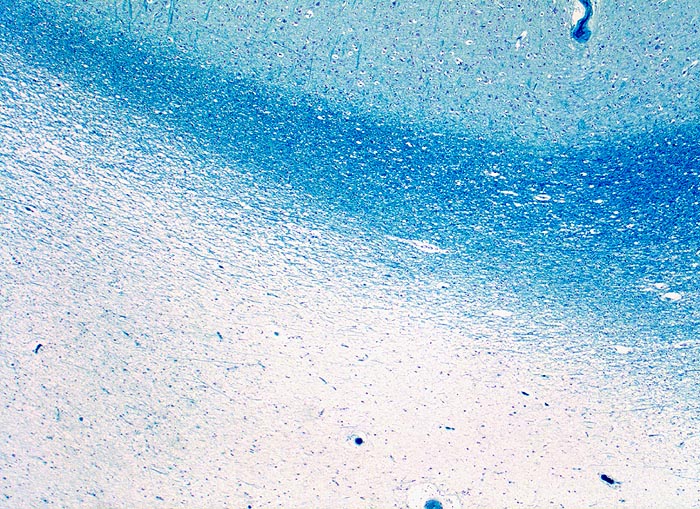

PathoPic – image database / PathoPic ID 5235 - Multiple Sklerose

Multiple Sklerose

Entzündung / Reparatur

Topographie

Hirn temporal

Beschreibung

Multiple periventrikulär gelagerte Entmarkungsherde im MRI

Histologie

Vergrösserung

25